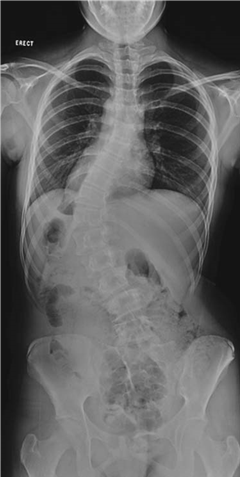

Describe what you see on these radiographs. What do you think is the most likely diagnosis?

When describing bone lesions remember: age; bone; site; matrix; margin; periosteal reaction; soft tissue mass; likely diagnoses.

The radiograph shows a lesion arising from the distal femoral metaphysis in a skeletally mature patient

The matrix of the lesion is mostly sclerotic, suggesting osteoblastic (bone-forming) activity; there are also a few small lytic (bone destruction) areas

The margins of the lesion are not clearly defined with a broad zone of transition into the surrounding bone

The cortex of the bone overlying the lesion is poorly defined and has been invaded by the lesion

The periosteum has been elevated anteriorly (Codmanโs triangle) and there is an associated โsunburstโ spiculation appearance

The lesion appears to have expanded out into the surrounding soft tissues

These features suggest that this is an aggressive, fast-growing, osteoblastic lesion of the distal femur โ the most likely diagnosis would be an osteosarcoma.